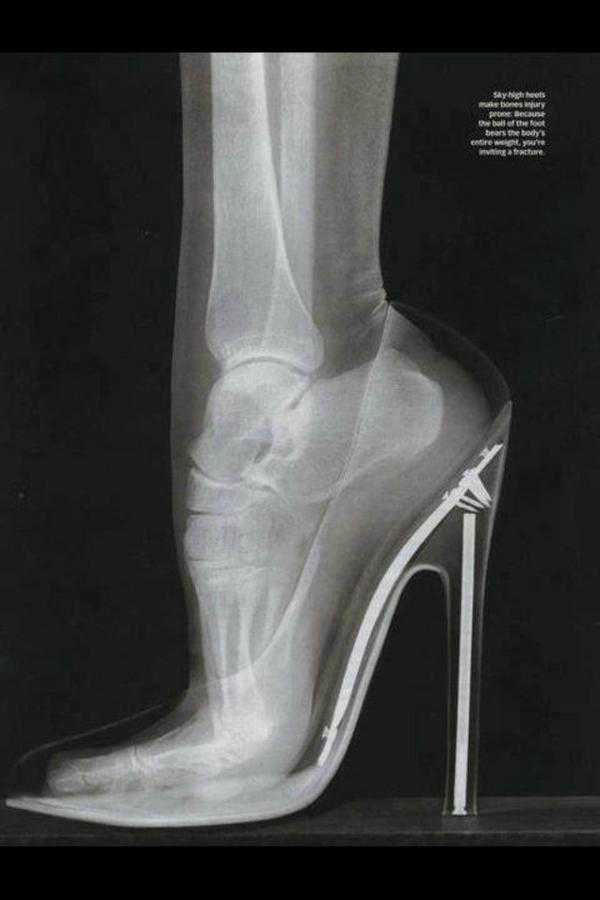

昔見たヒール履いたレントゲンの奴かなって思ってたらそれ以上のヒールだったのか・・・さすがに履ける人存在しないでしょ。

レントゲン写真 履いた時の足はこうなっている…

>>9

こういうの見るとやっぱりヒールって骨への負担が凄いよねー

ずっと履いてると骨が曲がったままになりそう

こういうの見るとやっぱりヒールって骨への負担が凄いよねー

ずっと履いてると骨が曲がったままになりそう

この骨の曲がり方が怖くていまだにヒールは履いたことないわ

この骨の曲がり方が怖くていまだにヒールは履いたことないわ

これ絶対足に悪影響だよね・・